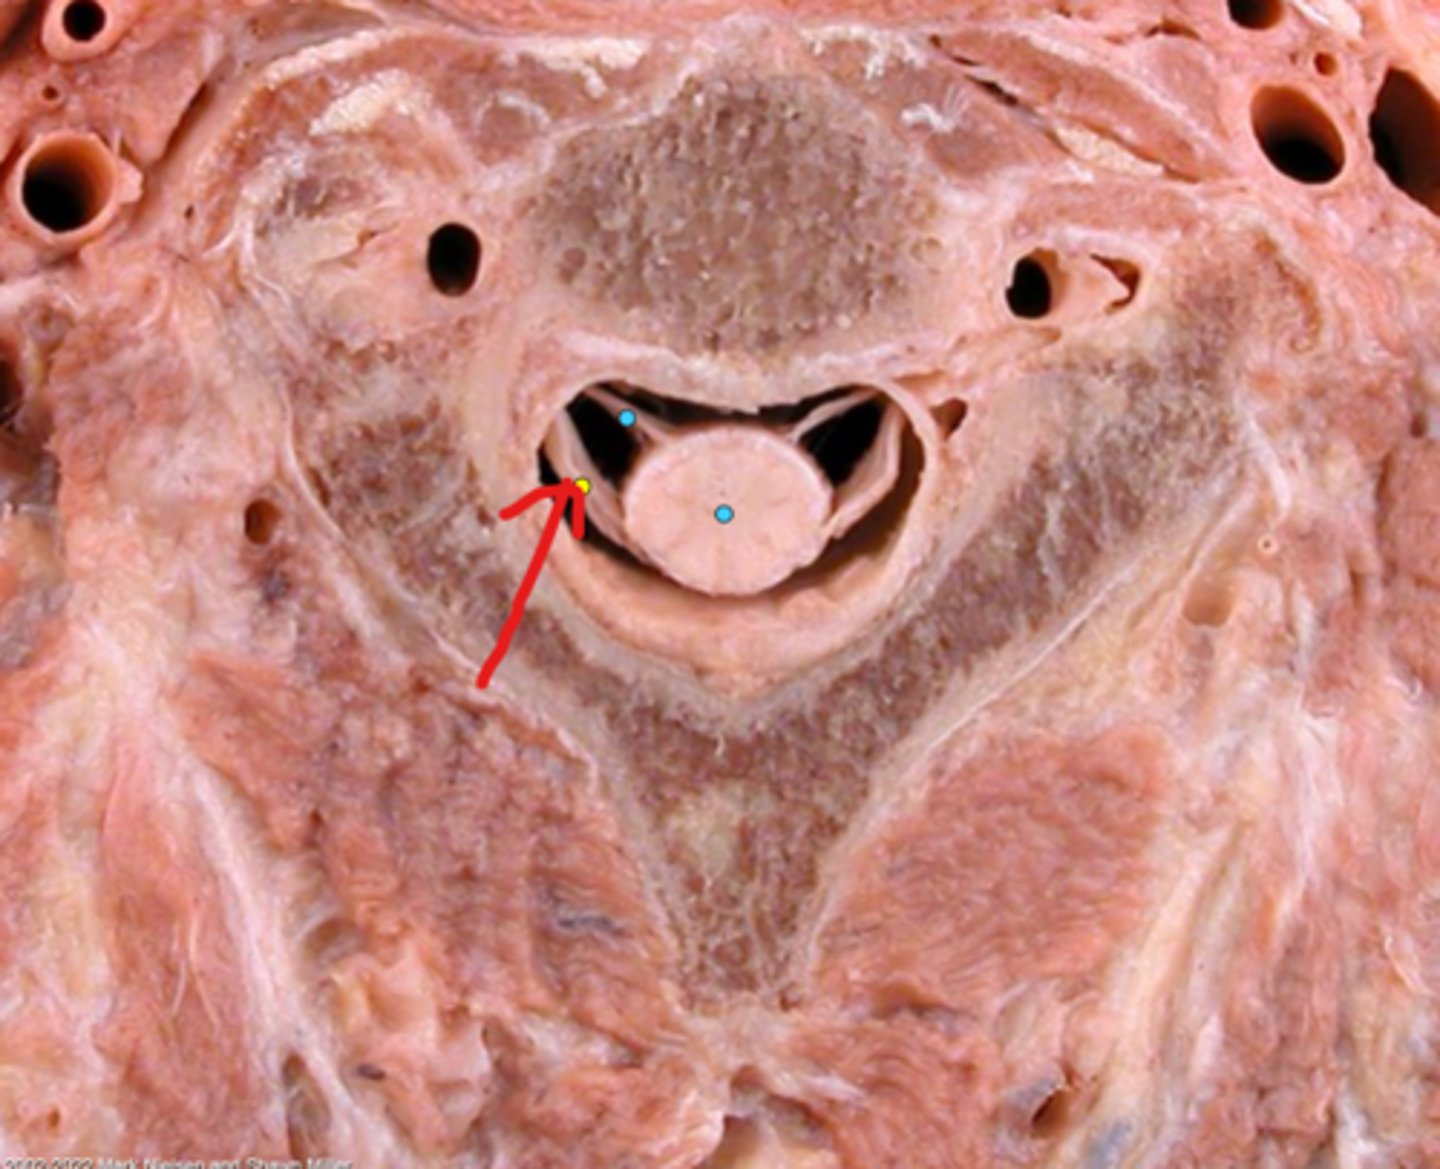

Vertebral foramen

White matter

Gray matter

Posterior (dorsal) rootlets

Anterior (ventral) rootlets

Spinal cord